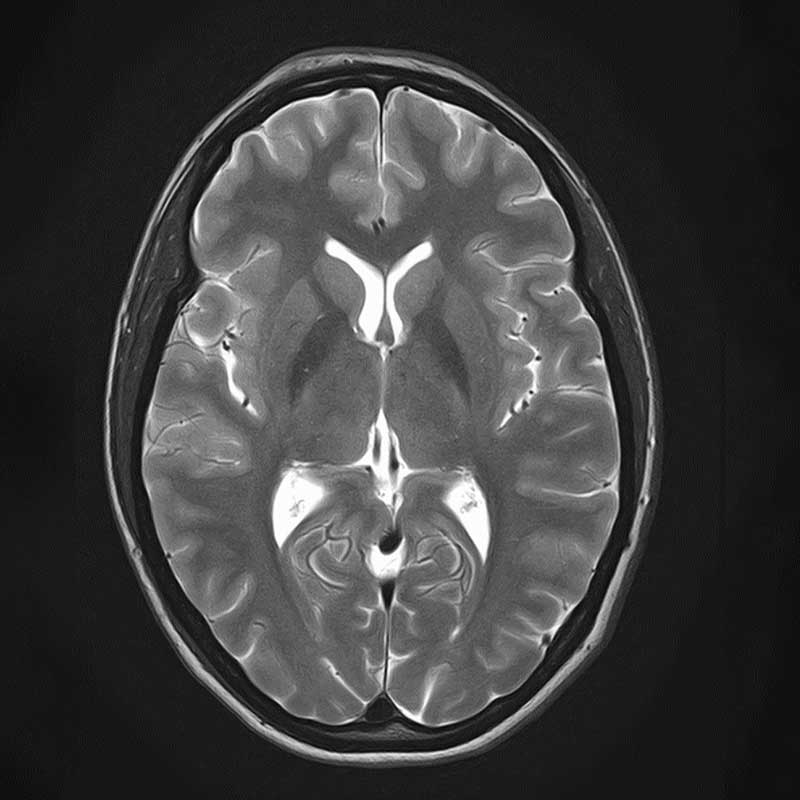

. Dies ist ein MRT-Bild eines menschlichen Gehirns in horizontaler Ansicht.

Protonen-gewichtete Sequenz des Neurokraniums

. Das Bild zeigt einen MRT-Scan des menschlichen Gehirns in axialer Ansicht.

Suszeptibilitäts-gewichtete 3D-Sequenz des Neurokraniums

. Ein MRT-Scan des Gehirns mit klaren Strukturen und Details der Hirnrinde.

Coronare Double Inversion Recovery Sequenz des Neurokraniums

Um Erkrankungen des Gehirns und der Wirbelsäule zu diagnostizieren, sind modernste Technik (MRT, CT) und ein hohes Maß an Spezialisierung erforderlich. Unsere Neuroradiologie setzt modernste Großgeräte für die Bildgebung des Zentralnervensystems (ZNS). Software- und Hardwareentwicklungen erlauben es, Hirnstoffwechsel und Hirndurchblutung optimal darzustellen. Wir haben uns daneben auf die neuroradiologische Diagnostik degenerativer, traumatischer und entzündlicher Gehirn- und Rückenmarksfragestellungen spezialisiert. Dabei kooperieren wir mit dem Asklepios Fachklinikum Göttingen bei psychiatrisch-neurologischer MRT-Bildgebung. Diagnostik und minimalinvasiver Therapie degenerativer Wirbelsäulenerkrankungen ist Teil unseres Wirbelsäulenzentrums.